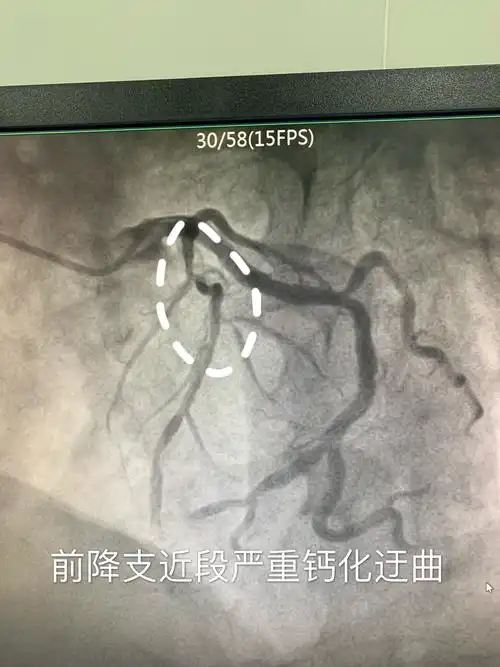

完善各项术前准备造影结束,冠脉造影显示前降支近段重度狭窄伴严重